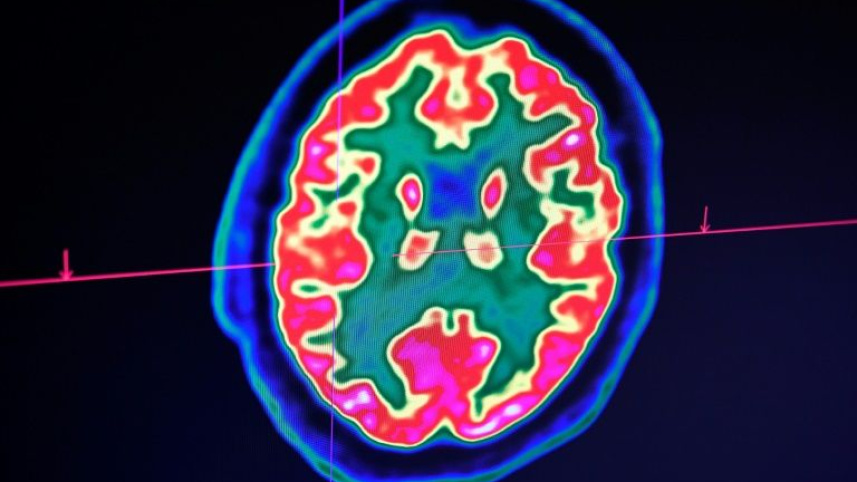

A paper in the New England Journal of Medicine this week examining 58 patients in Strasbourg, France found that more than half were confused or agitated, with brain imaging suggesting inflammation.

The man developed confusion and seizures, and imaging showed his brain was inflamed. But since this is the only known case so far, and the virus test hasn't yet been validated for spinal fluid, scientists remain cautious.

Her team is documenting striking cases including seizures in Covid-19 patients with no prior history of the episodes, and "unique" new patterns of tiny brain hemorrhages.

One startling finding concerns the case of a man in his fifties whose white matter -- the parts of the brain that connect brain cells to each other -- was so severely damaged it "would basically render him in a state of profound brain damage," she said.

Brain imaging and spinal taps are difficult to perform on patients on ventilators, and since most die, the full extent of neurologic injury isn't yet known.